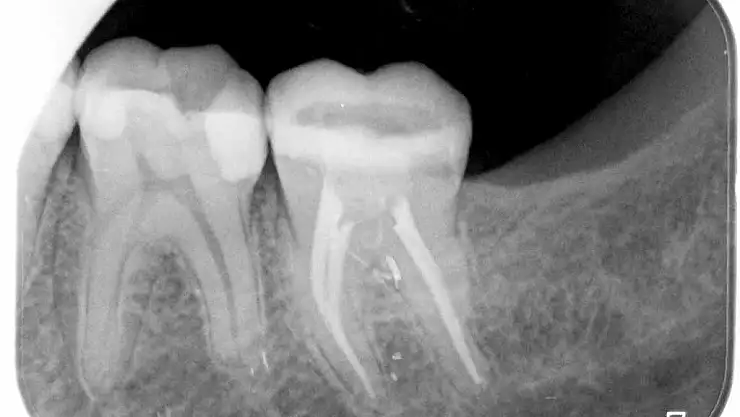

Elektronik Apex Bulucular

Kanal tedavisi ile ilgili başarıdaki en önemli etmenlerden biri kök kanal boyunun tam doğru olarak belirlenebilmesidir. Doğru belirlenemeyen kanal boyunda çalışıldığı zaman gerekli temizlik ve dezenfeksiyon işlemleri olması gerektiği yapılamaz. Bu türlü tedavilerde ise iyileşme elde edilemez. Eskiden kanal boyu belirleme için sadece filmlerden faydalanılıyordu. Fakat diş ve çevre dokuların anatomisinden de kaynaklı olarak filmler ile bu bilgi tam olarak elde edilememekteydi.

Elektronik apex bulucuları bu sorunu büyük ölçüde çözerek filmlere duyulan ihtiyacı azaltmış, hem daha iyi tedavi yapılmasına olanak sağlamış hem de maruz kalınan radyasyonu azaltmıştır. Bu cihazların kullanımı ile sinirleri dişe girdiği nokta tam olarak tespit edilebilir ve başarılı kanal tedavileri gerçekleştirilebilir.